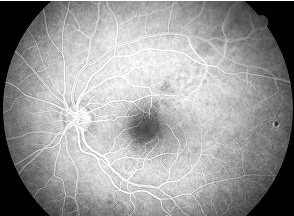

Diyabet tiplerinin belirlenmesinde ve tedavinin planlanmasında fundus floresein anjiyografi ( FFA ) çok önemli yer tutar. Hastanın kolundan damar içine boya maddesi verilir. Sonra hasta oturur pozisyondayken belli aralıklarla gözdibinin fotoğrafları çekilir. Hasta hiçbir ağrı duymaz, sonrasında evine gidebilir. Çekimden sonra ciltte sararma, idrarın turuncu olması normaldir. Bu, birkaç gün sürebilir. Bu tetkik yöntemi ile diyabetik hastalarda, damarlarda kaçak, tıkanıklık ve beslenme bozukluğunu saptamak mümkün olmaktadır.

Resim 5: Normal FFA görüntüsü. Damarlarda veya makulada herhangi bir sızıntıya ait parlak renkte beyazlık izlenmemektedir.